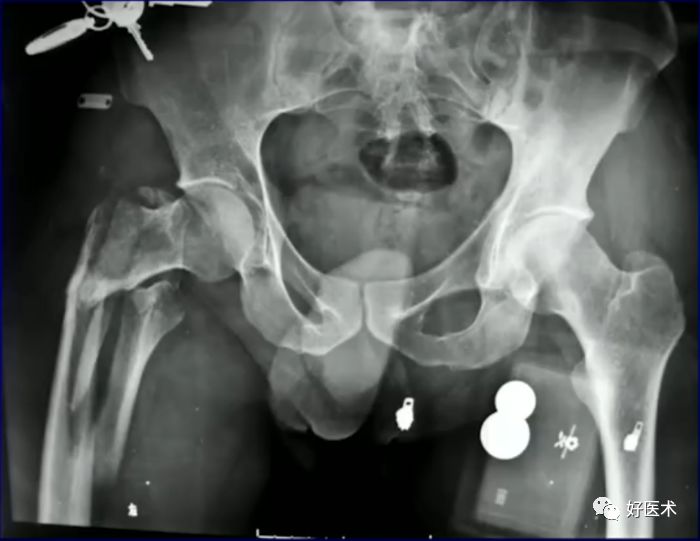

侧卧位行转子间骨折固定

病例:男,34岁,高处坠落伤,仅骨折余正常

处理方法:

-

髓内钉(开放VS闭合)

钢板

其他

术前牵引

开口、定位

术中过程